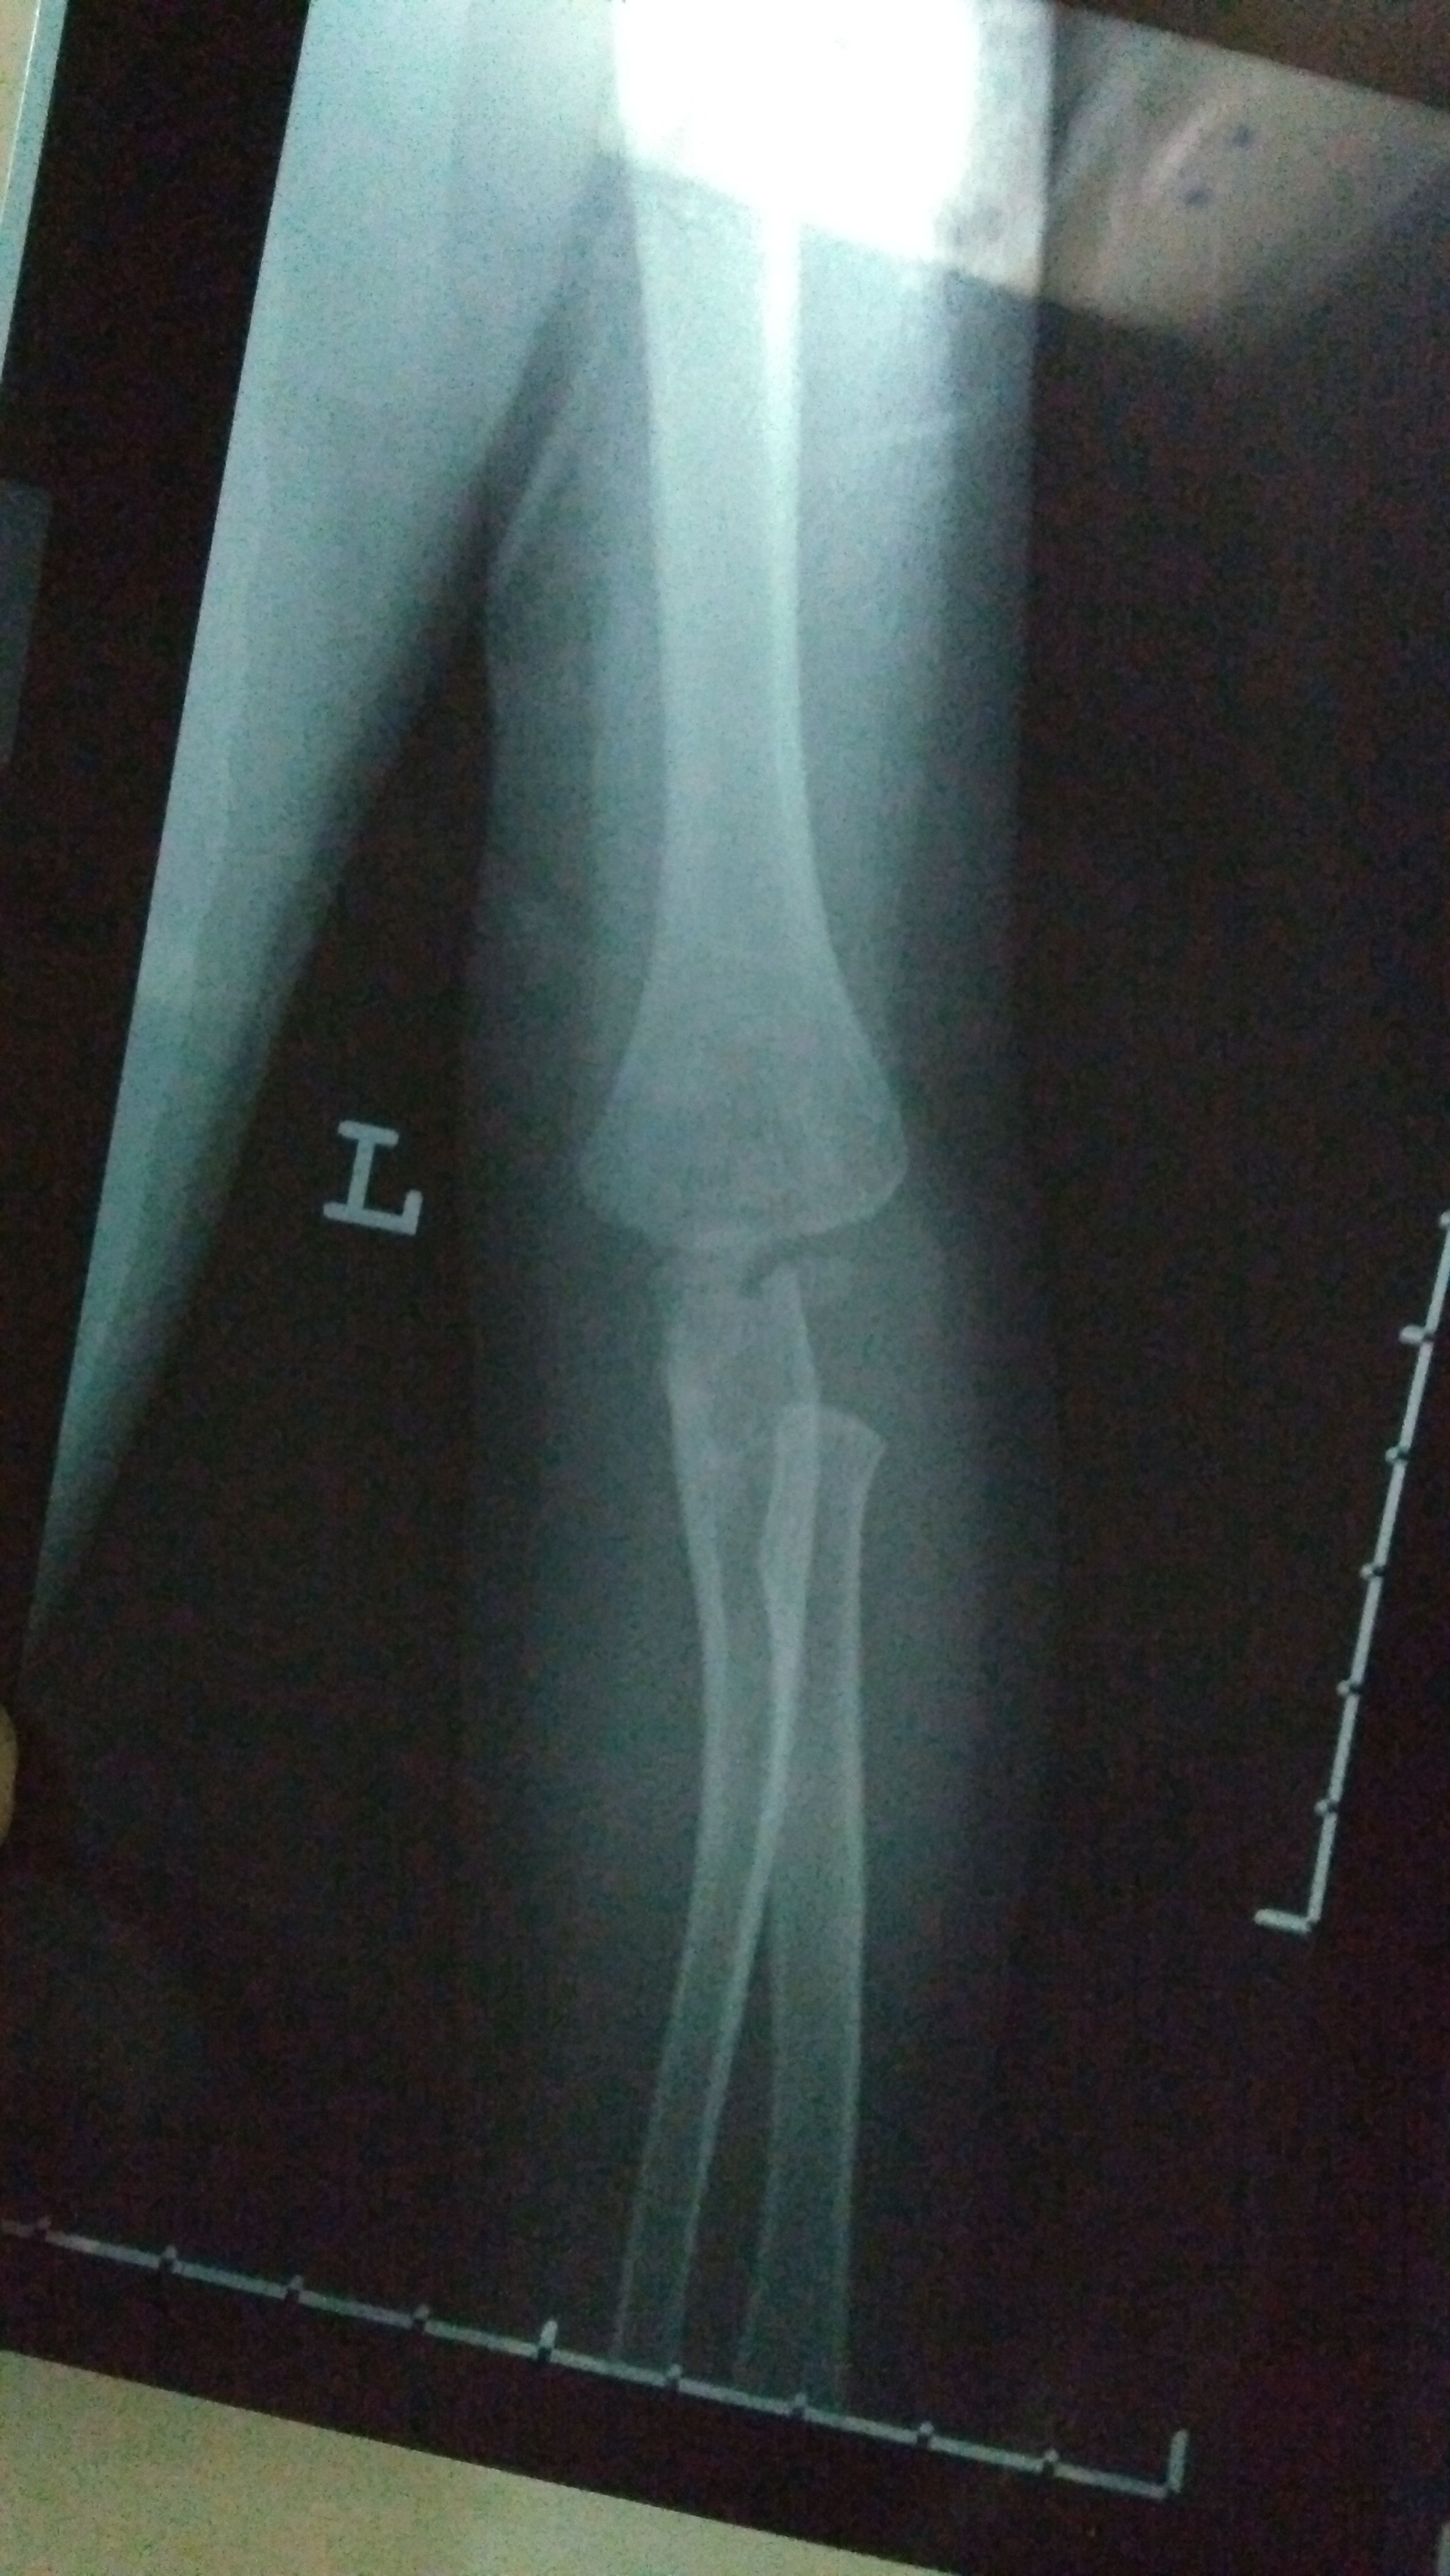

2岁宝宝骨折,急急急! 宝宝今晚玩耍奔跑时,摔倒姿势有异(速度很快不小心扑倒了,整个左手臂压在他自己身下,当时就骨折了)。 宝宝一直出冷汗表情痛苦哭,左手不动弹,我们赶紧去医院。以下是X光片(左手)和报告,打了石膏,医生让4-7天内去复查。 另外医生说小儿骨折这个部位骨垢骨折的情况比较少见,需要我明天带着片子报告去给他们主任看一下,看是否会影响手臂的功能性。如果有功能性影响,会影响孩子发育,还得纠正,做手术。 我知道医生总是会预先把最坏的结果告知患者,可是伤在儿身,痛在娘心。我担心害怕要做手术,加上回家后老公一直在说医生当时石膏没打好,让我带宝宝明天去重新打过石膏…说医生不太靠谱。确实,那个医生打石膏的时候还在接电话,一直不停跟他家人打电话接电话。 恳求有懂小儿骨折的医生帮帮我,看看我宝宝这个情况到底怎样?会影响他发育吗?可能要做手术纠正吗?跪求了!万分感谢!

这个部位骨折是非常清楚的,先打石膏固定一下(不可重复打石膏),看看恢复情况,如果效果不好一周之内要手术治疗!